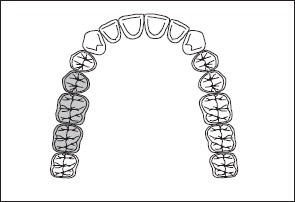

2. If the third molar is missing and not to be replaced, it is not considered in the classification (Fig 1-23).

Fig 1-23 If a third molar is missing and is not to be replaced, it is not considered in the classification. For purposes of this discussion, each tooth that is missing and to be replaced is shaded. Each tooth that is missing and not to be replaced is identified with an X. Hence, the illustration represents a Kennedy Class III arch.